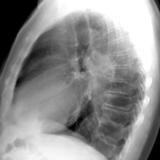

RLL collapse 4 PA

Date: 03/02/2006

Views: 3251

RLL collapse 4 Lat